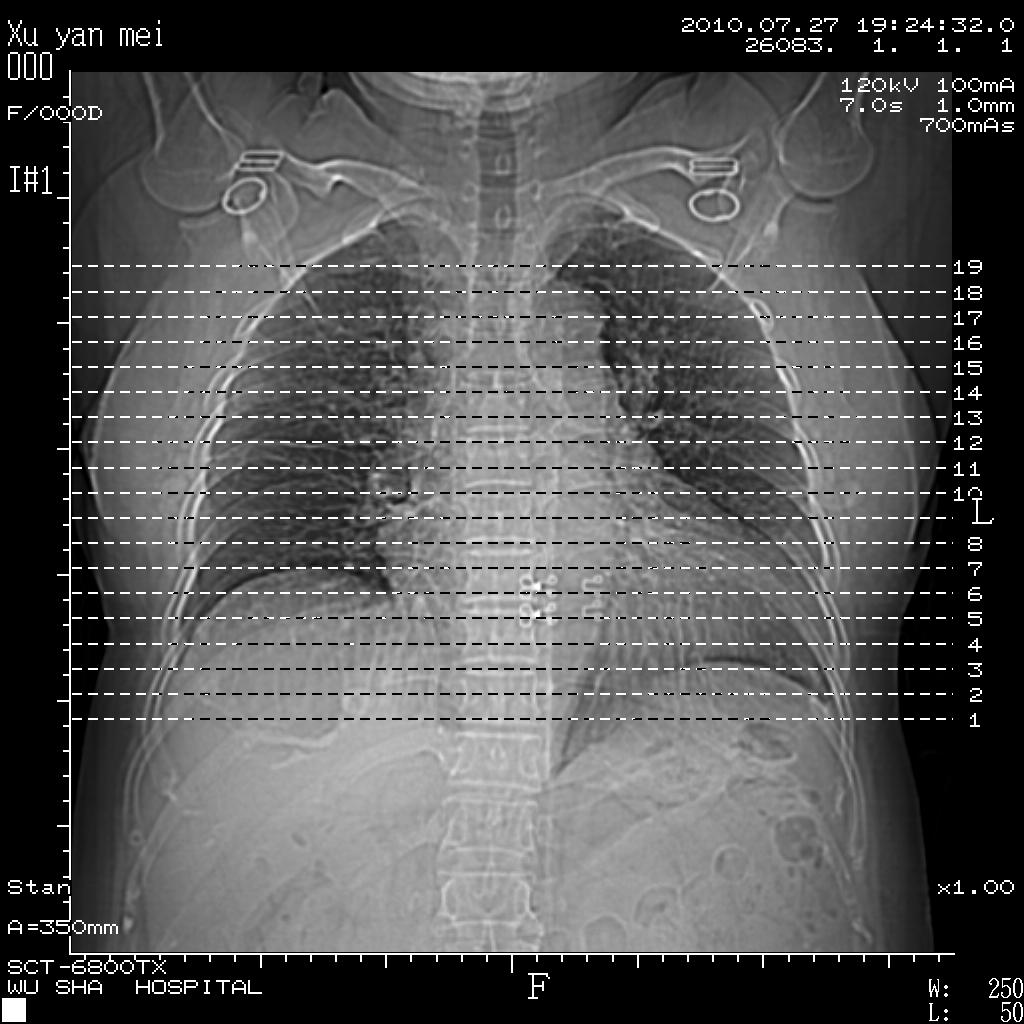

标题: CT27988:胸片容易漏诊啊 [打印本页]

标题: CT27988:胸片容易漏诊啊

女,60岁,胸痛就诊,右肺结核?炎症?其它?(胸片右侧中上肺野确实看不到什么啊)